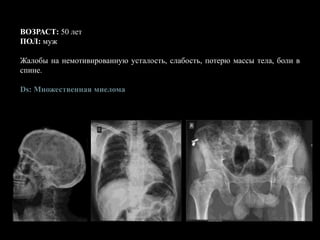

ВОЗРАСТ: 50 лет

ПОЛ: муж

Жалобы на немотивированную усталость, слабость, потерю массы тела, боли в

спине.

Ds: Множественная миелома